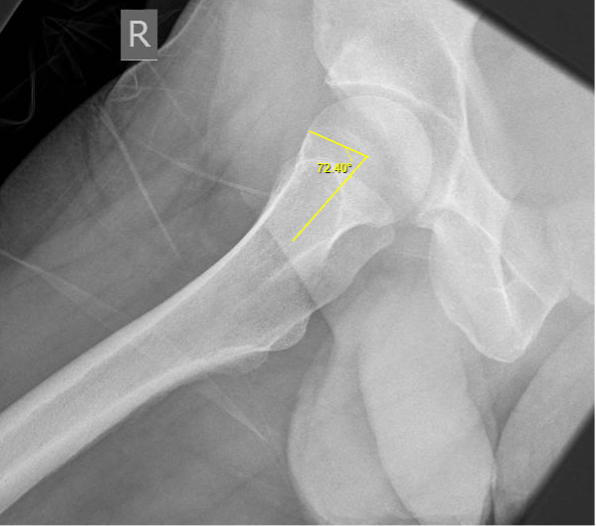

Radiologically, FAI is assessed with an anterior-posterior (AP) pelvis, and a cross table lateral hip radiograph. Besides the aforementioned morphological abnormalities, the asphericity of the femoral head neck junction and the crossover sign with the ischial spine sign indicate cam and pincer impingement respectively [12]. A Dunn view radiograph (taken in supine position with ipsilateral hip in 90° flexion and 20° abduction) is very sensitive to identify subtle cam deformities [13]. Alternatively, a frog-leg lateral radiograph can also be used to calculate the alpha angle to diagnose a cam type deformity [12]. The alpha angle is measured between one line intersecting the centre of the femoral neck and head, and another line intersecting the centre of the femoral head and the beginning of the prominence of the head-neck junction [6]. An alpha angle greater than 50 degrees indicates a cam type deformity (see Figures 1 and 2) [6].